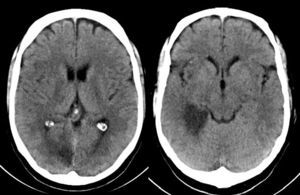

Case 1Our first patient was a 55-year-old man with a history of aortic valve disease, a mechanical prosthetic heart valve, and anticoagulation therapy with acenocoumarol. The patient visited the emergency department due to a one-day history of left leg paraesthesia progressing to the ipsilateral arm. He reported difficulties articulating words. In addition, his family described a mild transient deviation of the labial commissure, strange behaviours such as drinking from a bottle of oil and taking the same medication several times, incoherent speech, and short-term memory impairment. The patient was unaware of having exhibited any unusual behaviour over the previous days and was only worried about paraesthesia. Physical examination revealed disorientation in time, indifference towards his condition, left upper quadrantanopia, mild left upper limb paresis (4+/5) with ataxia, and left-sided brachiocrural hemihypaesthesia; plantar response was indifferent for the left foot and flexor for the right foot. A brain CT scan revealed hypodensities in the territory of the dorsolateral and temporoccipital thalamoperforating branches of the right posterior cerebral artery (Fig. 1). Upon admission, he presented multiple transient episodes of optical hallucinations. Images in the left visual hemifield were distorted (dysmorphopsia). He reported: ‘my wife's body seemed to stretch out and move away’ (macropsia and teleopsia), ‘people on my left side wore white clothes, and I saw white cars crossing my field of view’, ‘my wife seemed to be dressed in white but when she moved to my right side I could see the clothes she was actually wearing’. He saw geometric figures and inverted images in his left visual hemifield: ‘Images moved slowly and they sometimes seemed to freeze’ (palinopsia). An EEG revealed slow activity in the right posterior area, coinciding with the territory of the ischaemic lesion. We should note that the patient was aware that he was seeing optical illusions.